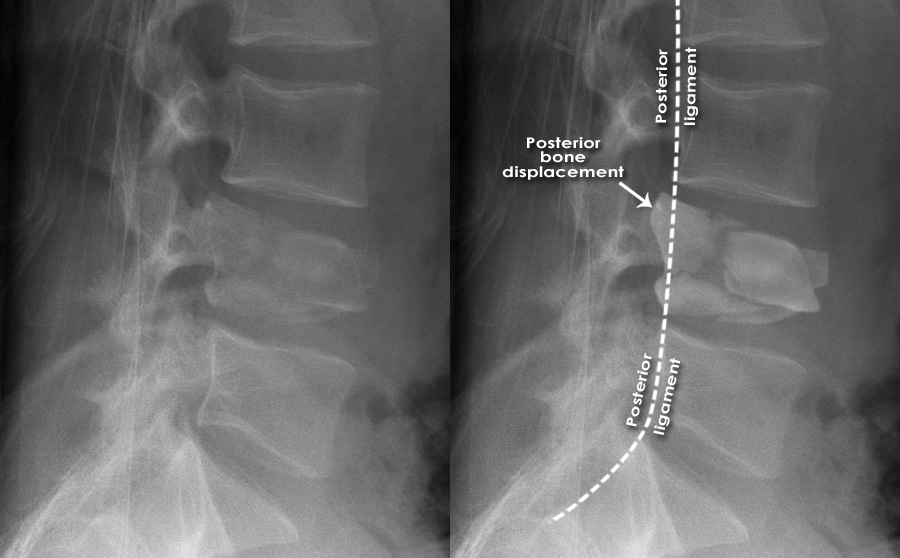

Fractured spine

Fractured spine 140 фотографий